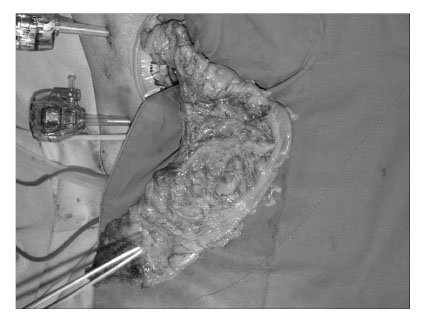

Fig. 2

Intraoperative photograph shows a localized dilatation of the rectosigmoid colon with normal colon proximally. Note also the dilated and tortuous mesocolic and serosal blood vessels.

Fig. 2 Intraoperative photograph shows a localized dilatation of the rectosigmoid colon with normal colon proximally. Note also the dilated and tortuous mesocolic and serosal blood vessels.